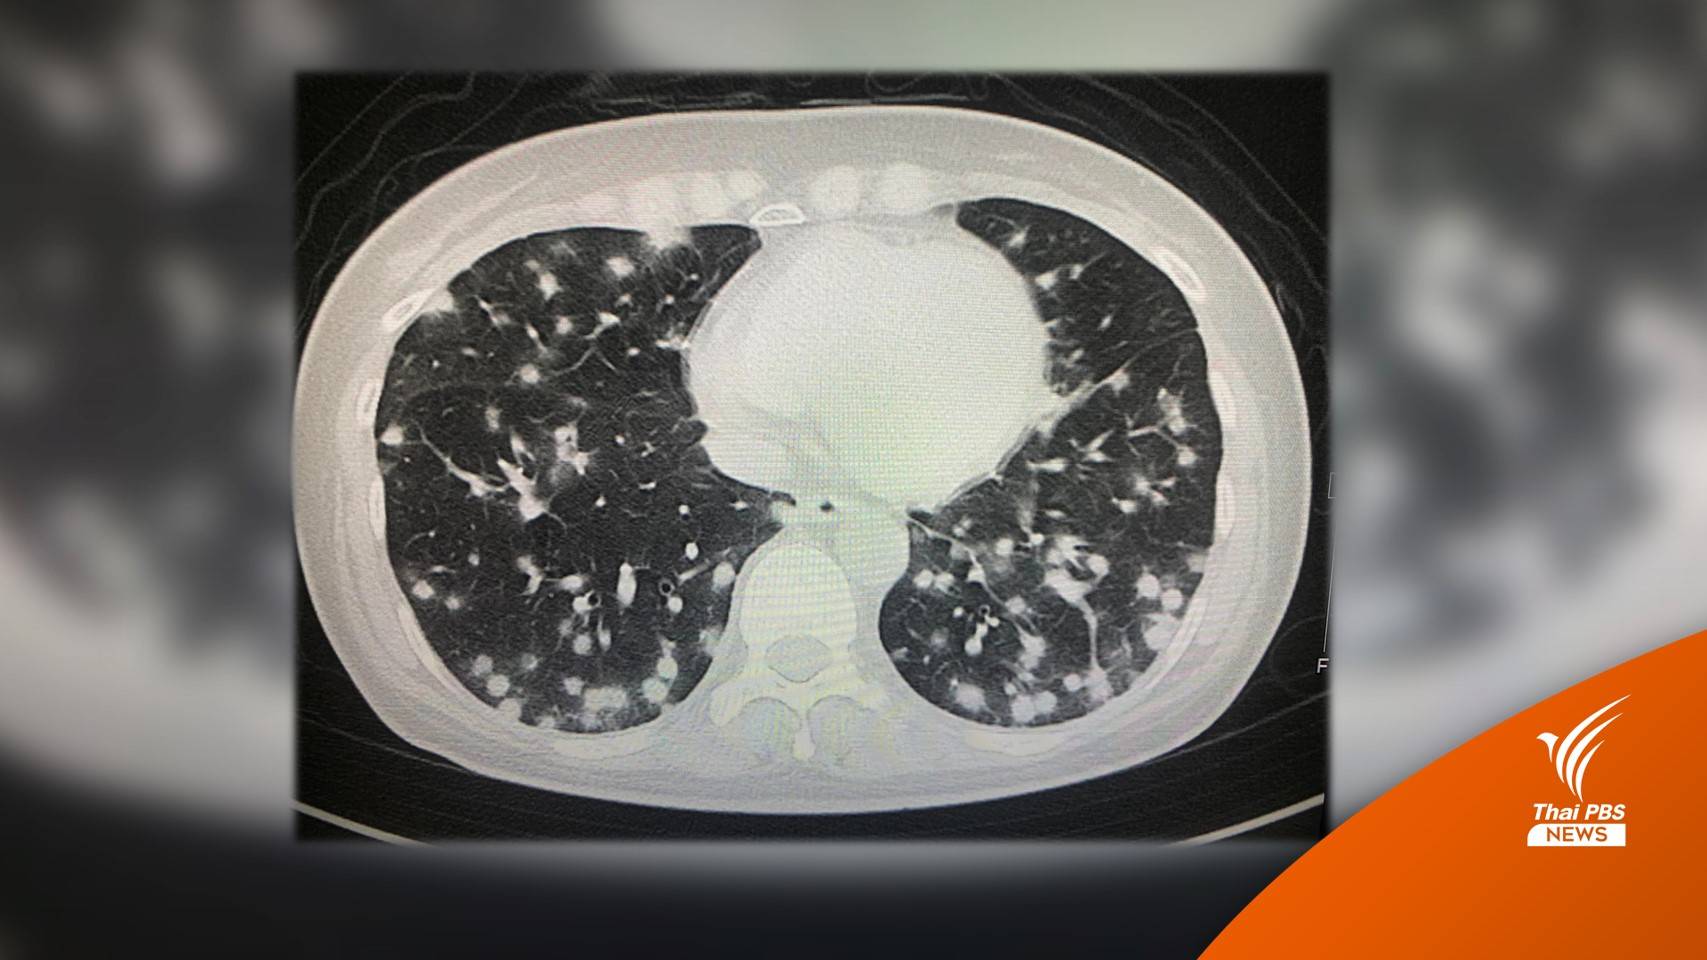

หลังจากนั้น 15 วัน เริ่มมีอาการไอแห้ง ๆ บางครั้งไอมีเสมหะสีขาว อ่อนเพลีย ไม่มีแรง เดินขึ้นบันไดเหนื่อย เบื่อหาร น้ำหนักลด 2 กิโลกรัม ไม่มีไข้ ไม่ปวดหัว ไม่ปวดกระดูก ไปหาแพทย์วันที่ 5 ก.ย.2565 เอกซเรย์ปอดผิดปกติ มีก้อนเล็ก ๆ กระจายทั่วปอดทั้ง 2 ข้าง ทำคอมพิวเตอร์สแกนปอด และช่องท้อง พบก้อนเล็ก ๆ ในปอดกระจายทั่วปอดทั้งสองข้าง

ก้อนในปอดด้านล่างขนาดใหญ่ถึง 1 เซนติเมตร พบก้อนในต่อมหมวกไตข้างซ้ายขนาด 0.5 x 1.1 เซนติเมตร และม้ามโตเล็กน้อย ได้ทำผ่าตัด ตัดชิ้นเนื้อจากปอดด้านซ้าย ส่งตรวจทางพยาธิวิทยา พบว่ามีเนื้อเยื่อตายและการอักเสบแบบแกรนูโลมา (necrotizing granulomatous inflammation) ไม่พบวัณโรค ย้อมสีพบเชื้อราลักษณะเป็นยีสต์ เพาะเชื้อราขึ้น Histoplasma capsulatum มีลักษณะเป็นราสาย Histoplasma อยู่ในกลุ่มรา 2 รูป (Dimorphic) อยู่ในเนื้อเยื่อมีรูปเป็นยีสต์ อยู่ในธรรมชาติมีรูปเป็นเส้นใยราสาย